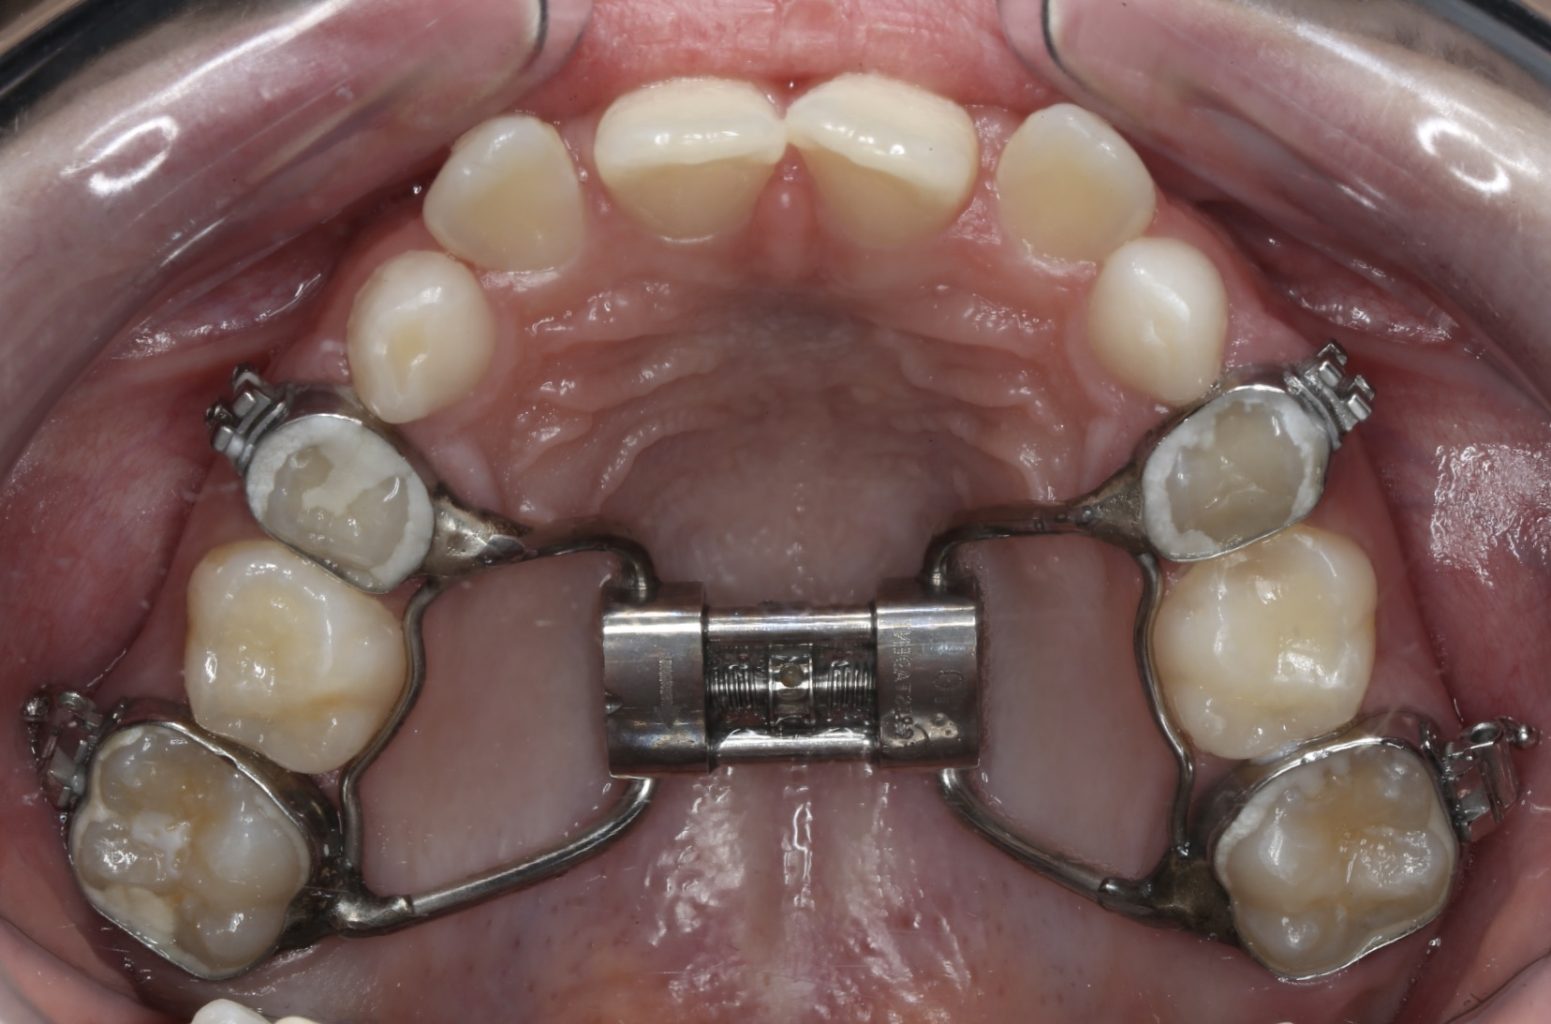

De Hyrax, ook wel ‘Rapid Maxillary Expansion’ (RME) genoemd, verbreedt vlot een te smalle bovenkaak. Deze beugel wordt ook wel ‘spin’ genoemd of meer poëtisch ‘vlinderbeugel’.

De Hyrax wordt in de regel gemaakt op 4 ringetjes om kiezen in de bovenkaak. Hij zit vast in de mond. Deze beugel mat thuis geleidelijk in de breedte bijgesteld worden. Wij oefenen dat met u.